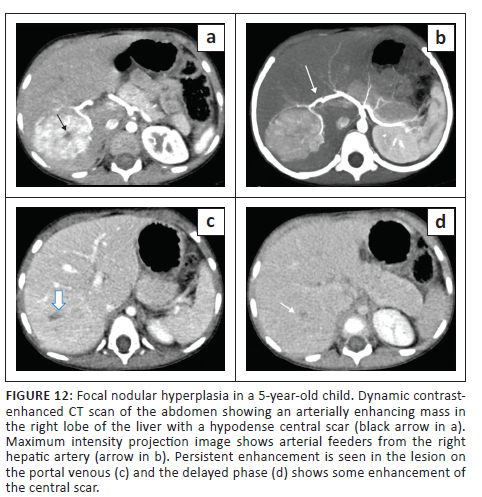

Typical features of FNH on CT are a round hypo- to isodense mass on NCCT that demonstrates homogeneous enhancement in the arterial and early portal venous phase (more than the liver parenchyma) and appear isodense to the adjacent liver parenchyma on the delayed phase. The central scar is usually hypoenhancing in the arterial phase and shows enhancement on delayed phase images. The central scar does not show calcification (differentiating it from fibrolamellar carcinoma [FLC]) (Figure 12). Atypical features like peripheral enhancement, washout in portal venous phase or lack of enhancement of the central scar on delayed phases scan warrant biopsy of the lesion.25,26